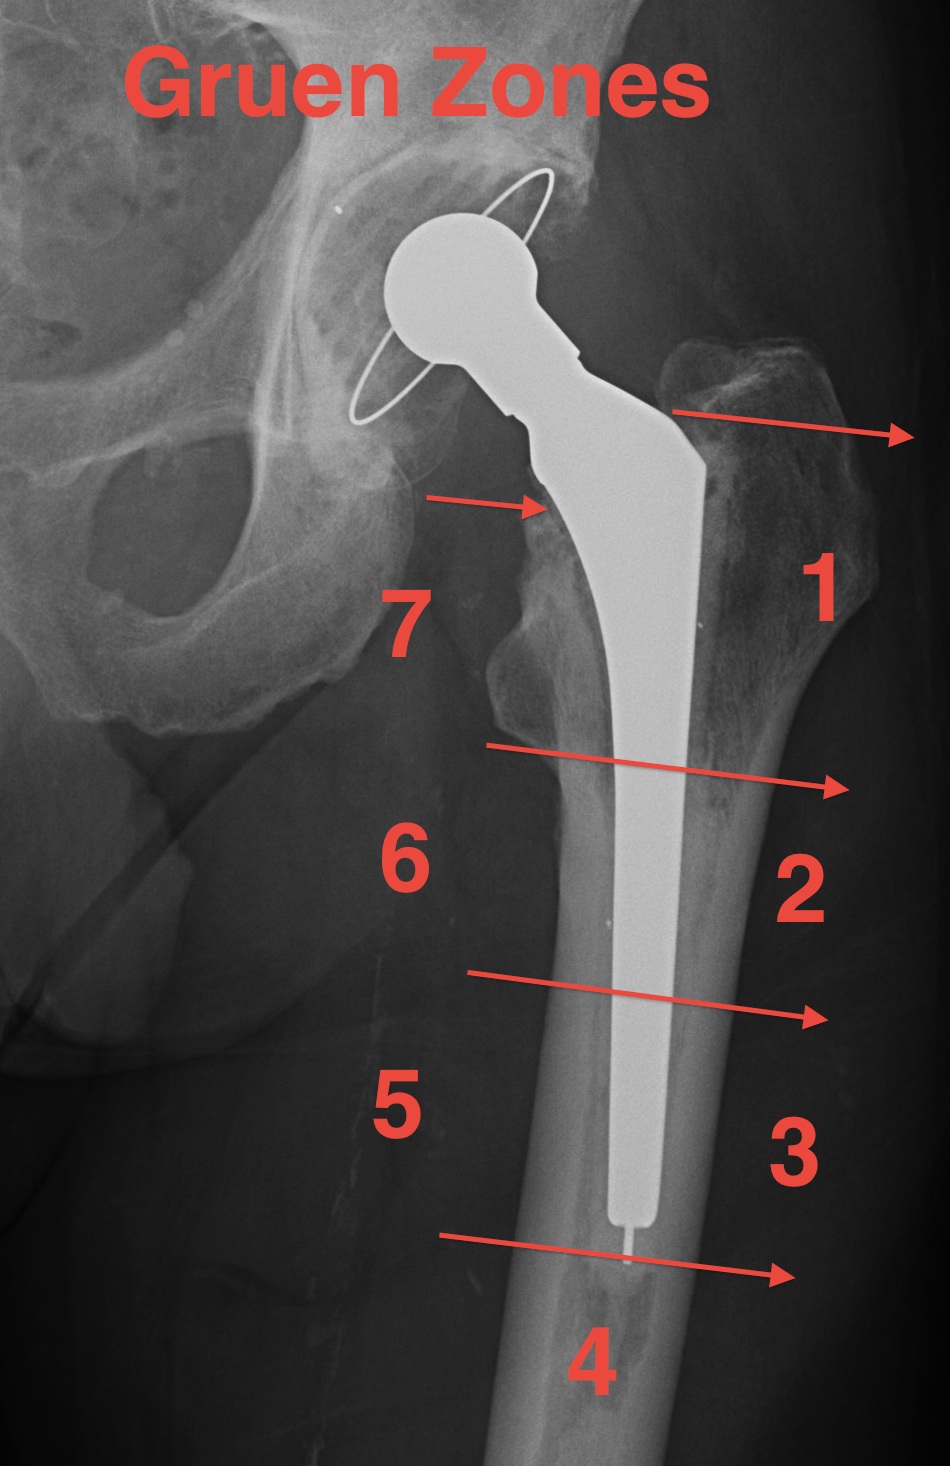

Lucent Zones

Gruen Zones

Femur:  Gruen Zones

AP 1-7

Zone 1:   Greater trochanter

Zone 4:   Tip

Zone 7:   Lesser trochanter

Lateral 8-14

Zone 8:   Anterior-superior

Zone 11: Tip

Zone 14: Posterior-superior